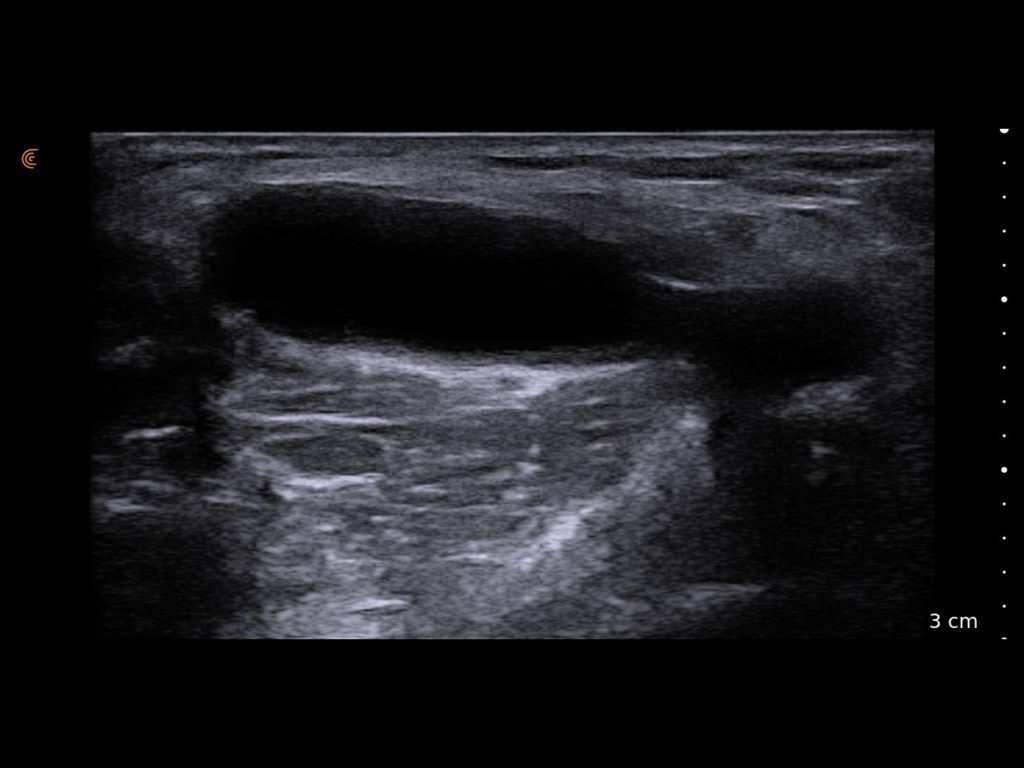

Elevate your sports medicine practice with high-definition dynamic imaging of muscles, joints, and tendons for accurate diagnostics and guided interventions on and off the field.

You can carry it from office to office, put it in your lab coat and use it on pain rounds. The image quality is superior.